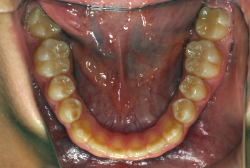

叢生(そうせい)

凸凹な歯並びのことを叢生といいます。矯正歯科に来院する患者様の主訴の中で、最も多いのが「配列の凸凹を真っ直ぐにしたい」というものです。歯の大きさと顎の大きさの調和がとれていないことが原因です。

凸凹を主体としたケースの場合、当院の平均治療期間は18ヶ月ですので、このケースは少し長めに経過しました。理由の一つは凸凹の程度がかなり重症だったと言うことですが、もう一つは、右下第2大臼歯が45度くらい前傾していたため、それを整直化させるために時間を要したと考えています。いずれにしても最終結果は大変よい状態と思います。

治療前は並びが乱れて見た目が悪いというのはもちろん問題ですが、歯科医学的に一番困るのは噛み合わせが悪いという点です。上下の犬歯(3番目の歯)は、上下的に離れた位置にあるため接触することができません。つまり歯としては存在していても、歯としては機能していないということです。